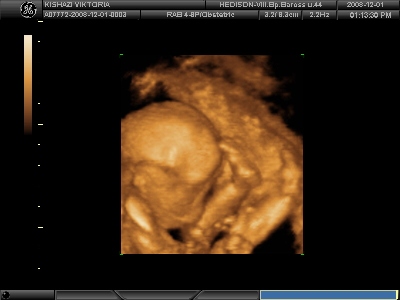

Ha már a kíváncsiságnál tartunk, bejelentkeztem péntere 4D-s UH-ra. :lol: Nem bírjuk kivárni, míg megtudjuk a gyerek nemét. Tüncinél türelmesebbek voltunk, és nem is voltunk 4D-n.

Kép